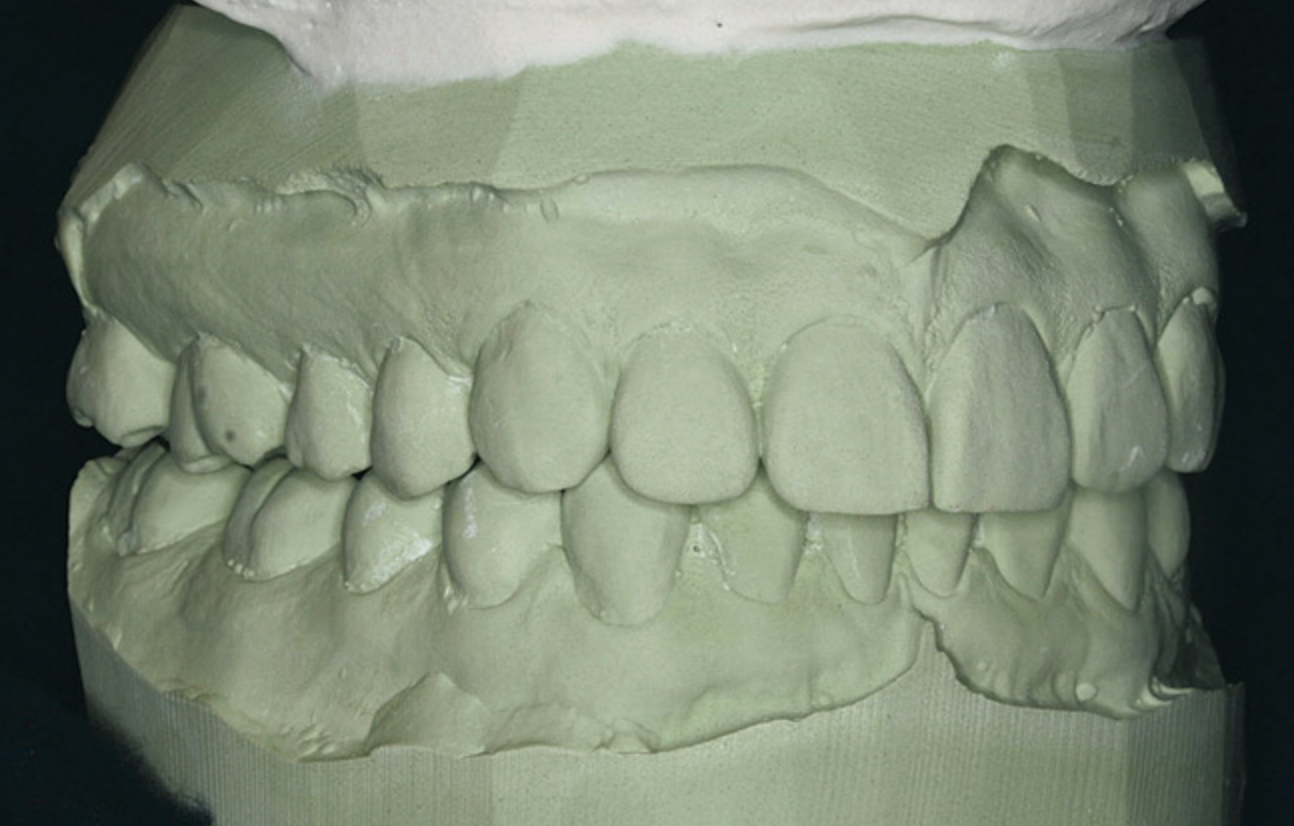

Figure 3  There is a mesial inclination of the maxillary teeth from gingival to occlusal in the esthetic dentition. Maxillary posterior teeth have an axial inclination which converges from the gingival through the occlusal toward a central fulcrum.

Figure 3

All teeth have a characteristic axial alignment that creates esthetic balance. The restorative dentist can alter the appearance of the inclination by reshaping the tooth or with a restoration (Figure 3). However, orthodontic tooth movement can make significant improvements in axial position on a routine basis. The orthodontist should always attempt to set the alignment to the best advantage for the restorative dentist.

While most orthodontists appreciate anterior dental esthetics, some do not consider that the posterior teeth also have a normal alignment angle. The posterior teeth axial line angles appear to converge from the gingival through the occlusal toward a “central fulcrum.7 Alignment of teeth with significant crowding without extractions may cause a flaring of the axial alignment of both anterior and posterior teeth. If orthodontists do not extract teeth or reduce the width of teeth with interproximal reduction when the dental arch perimeter is greater than the skeletal arch perimeter, the teeth will be tipped, creating a “flared” appearance. Tipped teeth are not only esthetically unappealing, they are not centered in bone and do not allow occlusal forces to be directed down the long axis of the root, which impairs long-term stability (Figure 4). If treatment goals cannot be reached without extractions, then extractions must be considered.